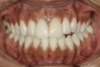

Il s'agit d'un cas d'une chute avec expulsion de l'incisive centrale droite et fracture de l'incisive centrale gauche.

Un implant avec greffe osseuse a été posé en site de l'incisive droite et une facette sur dent dévitalisée sur l'incisive gauche.

La réalisation a été faite par un laboratoire meilleur ouvrier de France.